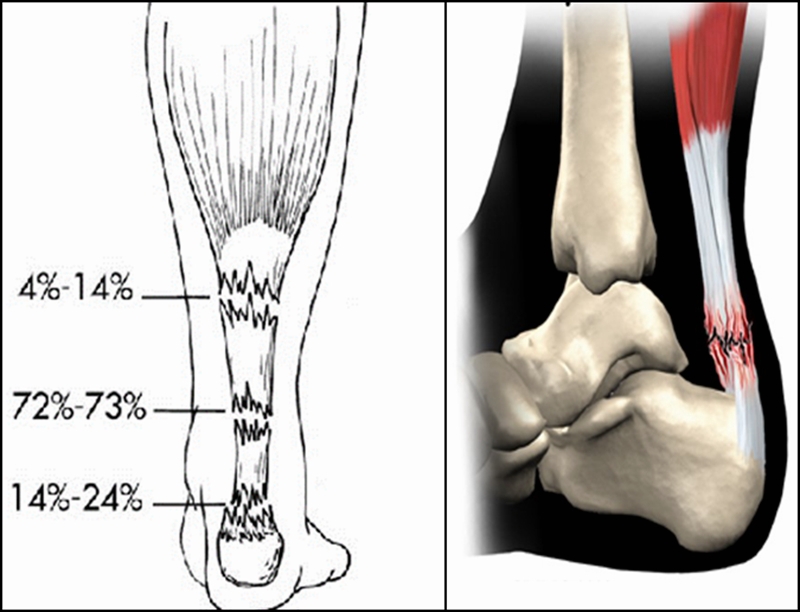

跟腱是人体最长、最强壮的肌腱,起于腓肠肌和比目鱼肌,止于跟骨结节,长约15cm。它在腱的背侧约有4-8层润滑层,位于深筋膜与腱组织之间,每层有独自的营养血管。具有踝关节跖屈,完成脚尖站立、正常走路、跑、跳、上下楼梯等动作的功能。

跟腱断裂容易发生于偶尔参加运动的中年人,所以也称这类人为“周末运动员”。踝在过伸位突然用力,断裂多发生在跟腱止点上方2~6cm,因为跟腱自上而下逐渐变窄增厚,跟骨结节上方2~6cm处最窄,此处最薄弱。

跟腱营养动脉造影显示,下段区域血供相对较少,跟腱中的血管数随年龄的增大而逐渐减少。